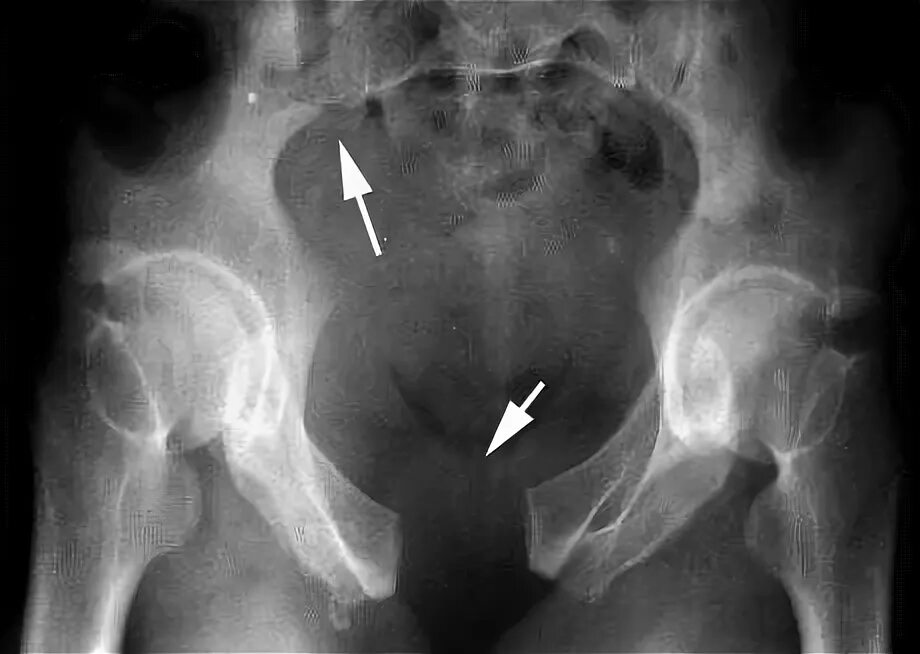

Разрыв крестцово подвздошного сочленения